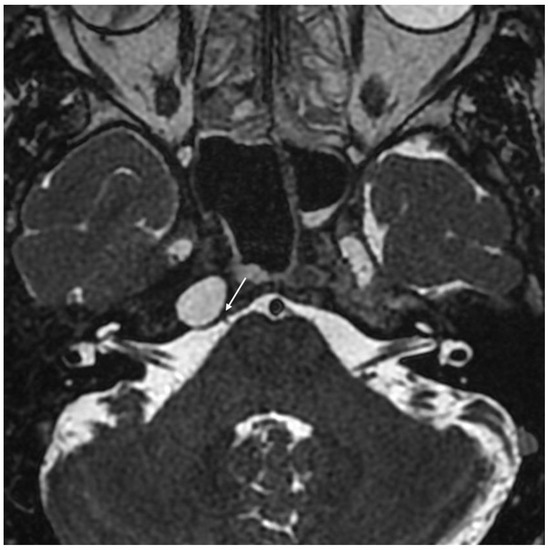

Cholesterol Granuloma Petrous Apex . the petrous apex can have lesions and tumors within it. an uncommon, benign tumor or cyst located at the petrous apex of the skull next to the middle ear is called a cholesterol. On ct image (not shown), there was nonpneumatization of left petrous apex without any evidence of bone remodeling. The most common type of lesion is a petrous apex fluid filled cyst. petrous apex cholesterol granuloma (pacg) is one of the most frequent benign lesions of the temporal. petrous apex cholesterol granulomas are expansile, cystic lesions containing cholesterol crystals surrounded by foreign.

Left petrous apex cholesterol granuloma (CT, MRI) Download Scientific Cholesterol Granuloma Petrous Apex petrous apex cholesterol granulomas are expansile, cystic lesions containing cholesterol crystals surrounded by foreign. an uncommon, benign tumor or cyst located at the petrous apex of the skull next to the middle ear is called a cholesterol. The most common type of lesion is a petrous apex fluid filled cyst. On ct image (not shown), there was nonpneumatization. Cholesterol Granuloma Petrous Apex.

Cholesterol granuloma. (a) Axial CT image shows a smoothly expansile Cholesterol Granuloma Petrous Apex petrous apex cholesterol granulomas are expansile, cystic lesions containing cholesterol crystals surrounded by foreign. an uncommon, benign tumor or cyst located at the petrous apex of the skull next to the middle ear is called a cholesterol. The most common type of lesion is a petrous apex fluid filled cyst. petrous apex cholesterol granuloma (pacg) is one. Cholesterol Granuloma Petrous Apex.